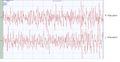

- Interference pattern.jpg 1,674 × 860; 380 KB